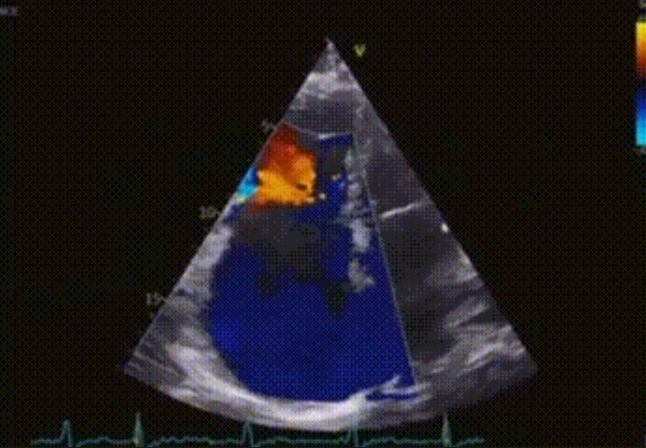

術前心臟超聲提示:極重度三尖瓣返流,右房容積明顯增大,三尖瓣瓣環顯著擴張。

術后心臟超聲提示:LuX-Valve Plus植入后,三尖瓣瓣環處可見人工瓣膜回聲,未見返流,人工瓣膜穩定,瓣葉開閉良好,連續多普勒估測三尖瓣平均跨瓣壓差僅為1mmHg。